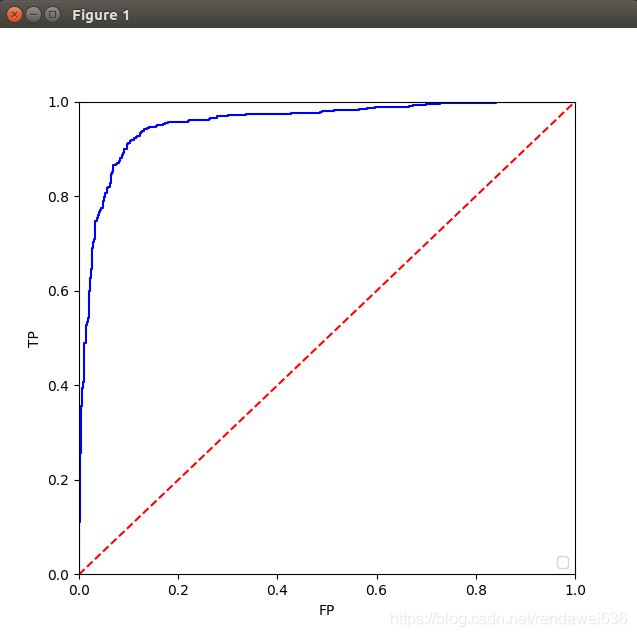

三、训练结果

我们从数据库中,标记了大概11000个肺结核,11000个负样本。ROI图如下